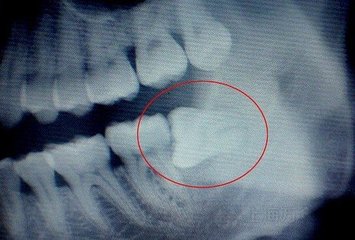

因為(wei) 罪魁禍**其實是智齒,並不是單獨的炎症,所以需要拍片查看智齒具體(ti) 是什麽(me) 情況, 有沒有蛀牙或者是引起鄰牙蛀牙,有沒有對咬牙,以及位置正不正,是不是經常發生炎症,一般如果有兩(liang) 個(ge) 或者一個(ge) 不符合,就可以考慮拔除智齒。